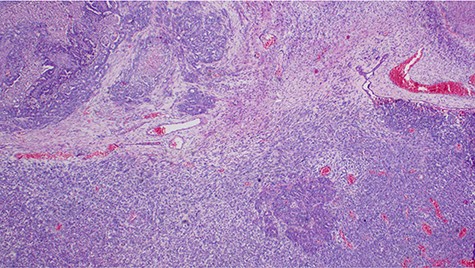

Histopathology of the tumor showing malignant epithelial and sarcomatous elements, hematoxylin and eosin, ×40 magnifications.

Malignant mixed Müllerian tumor of the ovary is a rare tumor that accounts for ~1% of all ovarian cancers [1, 2]. These tumors are typically large, ranging from 10–20 cm in diameter; our patient’s tumor was 15.6 × 7.1 × 6.1 cm (Fig. 3). The presence of an intimate admixture of malignant epithelial and stromal elements (Figs 4, 5) is the morphological characteristic feature of this tumor. The epithelial element is most commonly a high-grade serous or endometrioid carcinoma, but can be of any of the surface epithelial cell types of ovarian tumors. The stromal component usually contains sheets of hyperchromatic rounded to spindled cells with marked nuclear atypia and a high mitotic index (Fig. 5). Immunohistochemical stains for epithelial markers are often positive in the sarcomatous component, as it has been observed in the index case (Fig. 6), and their behavior and patterns of spread are similar to high-grade serous carcinomas [3–5].